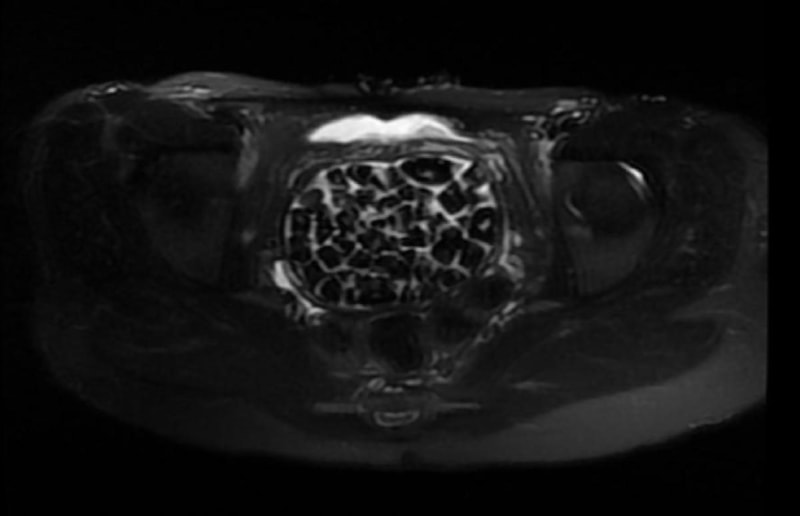

Hastasının durumuna yönelik konuşan Üroloji Uzmanı Doç. Dr. Erkan Erkan, "Hastamızın 2004 yılında doğduğunu ardından doğar doğmaz ekstrofi vezika dediğimiz 50 binde bir görülen bir anomaliden dolayı art arda ameliyatlar geçirdiğini öğrendik. 10 yaşında yine bir ameliyat geçirmişti, gerekli görüntüleme ve tetkiklerimizi yaptırdık. Normalde mesanesinin olması gereken yerin hemen arka kısmında taşlarla dolu bir kese olduğunu gördük, bunun üzerine ek görüntülemeler; MR çektirdik. Hastamız çelişkili açıklamalar almıştı, kendi radyolojik kliniğimiz ve edindiğimiz konsültasyonlarda taşların mesanede değil vajinal boşlukta oluştuğunu düşündük, bir planlama yaptık.

Kadın doğum hocamızın da çabasıyla taşları tamamen temizledik ardından ileride normal bir hayat sürmesi bakımından oraya plastik cerrahi yaptık. 287 adet taş çıkardık, pratikte gerçekten görünce çok şaşırdık çünkü bu aynı zamanda literatürde çok nadir görülen bir olay. Biz ameliyata hazırlanırken de teorik olarak biraz araştırdık. Literatürde gördüğümüz kadarıyla buna benzer bu tanıma uyan bir vaka vardı. Literatürde sanırım yayınlanmış 2’nci vaka olacak. Farkındalık çok önemli, bilinçli bir hastamız vardı. Doğumsal anomaliyle doğan çocuklarımızda ileride bunlara bağlı bazı sıkıntılar çıkabileceğinin öngörülmesi lazım. İlgili tedavilerini alsalar bile düzenli takiplere gelmeleri gerekiyor. İleride eğer dikkat etmezse ki zannetmiyorum, tekrarlayabilir. Bu rahatsızlık ekstrofi vezikal epispadias durumu, çok nadir bir durum." dedi.

Genç kızın uzun süredir devam eden karın ağrısı olduğunu söyleyerek sözlerine başlayan Jinekolojik Onkoloji Uzmanı Op. Dr. Emin Erhan Dönmez, "Mesane taşları olduğu düşünülerek daha büyük bir hastaneye refere edilmiş. Aramızda mini bir konsey yaparak muayene ettik. Vajen bir hazne görevi görerek orada durağan bir idrar, uzun süre beklediği için idrar içindeki minerallerde çökerek taşlar oluşmuş. Mesanedeki idrarın vajene akmış olabileceği ve vajende göllenen idrar nedeniyle taşların burada oluşacağını düşündük, ameliyatımızı planladık. Ameliyata tanı amaçlı girmiştik, sistoskopi (Mesane gibi idrar yollarını kapsayan kısımlardaki rahatsızlıkların teşhis ve tedavisinde kullanılan endoskopik bir yöntem) dediğimiz ameliyatı Erkan Hocam ile birlikte gerçekleştirdik.

Önce mesaneyi bir görüntüledik, mesane tabanına yaklaşık 2-3 cm’lik bir alandan vajene fistülize olduğunu gördük. Mesaneden vajene geçtiğimiz esnada tüm vajenin taşlarla dolu olduğunu gördük. Tanı amacıyla girdiğimiz ameliyatta her şey de olağan gittiği için tedaviye geçtik. Taşların çıkabileceği kadar bir genişlik sağladık. Daha sonra yaklaşık en büyüğü 2,5 cm boyutlarında olan, irili ufaklı 287 tane taşı ameliyat esnasında çıkarmış olduk. Taşların tekrarlamaması için idrarın göllenmemesi, en azından dışarıya rahatça boşalabilmesi için vajinal rekonstrüksiyonu sağladık. Ameliyatta da herhangi bir problem yaşamadık. Literatürü Erkan Hocam ile birlikte değerlendirmiştik. Primer olarak vajende birikmiş olan bu kadar çok sayıda taşla ilgili bir makale görmedik, rastlamadık." dedi.